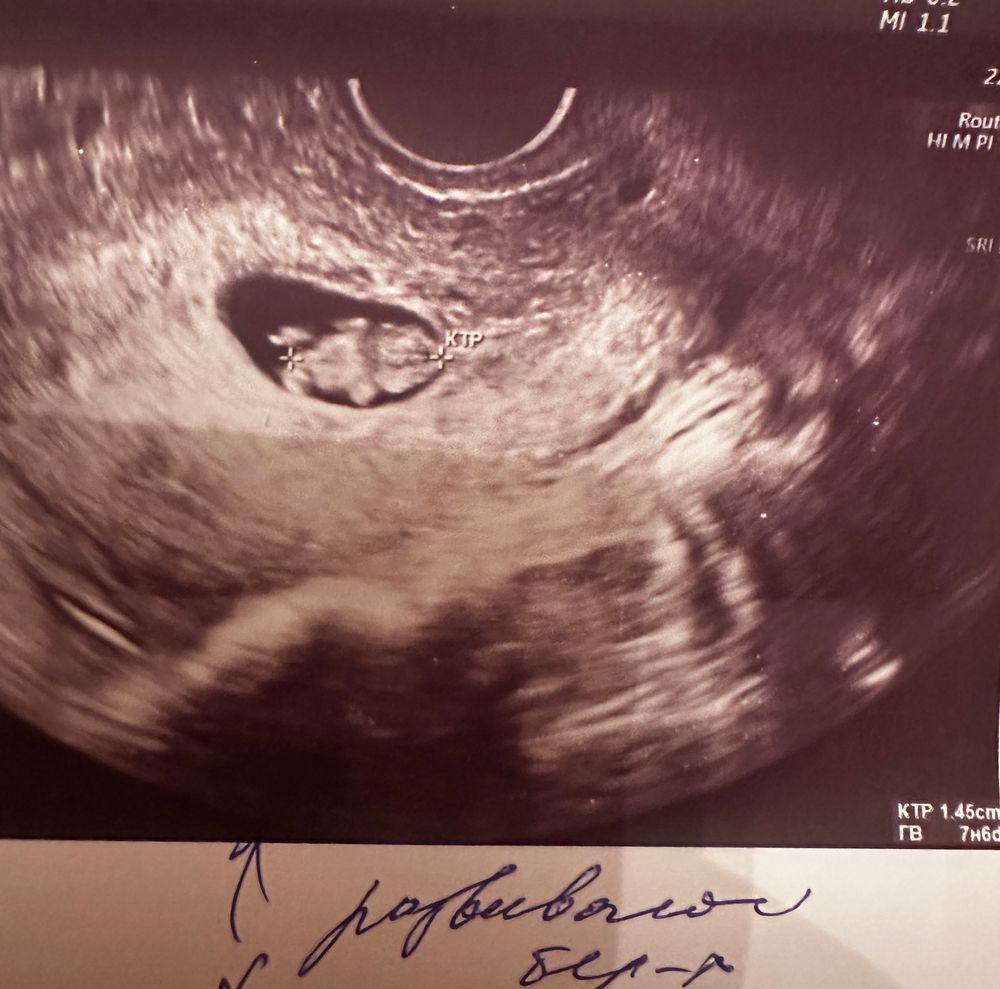

В 8+5 было так, фото с этого узи:

1 плодное яйцо с СВД-18,8мм. соотвт-бнедбдней, лоцируется эмбрион с КТР - 14,5мм., соответсвует 7 нед. бдня. С/б визуализируется. ЧСС -167 уд\мин. Желточный мешочек d-4,1 мм;